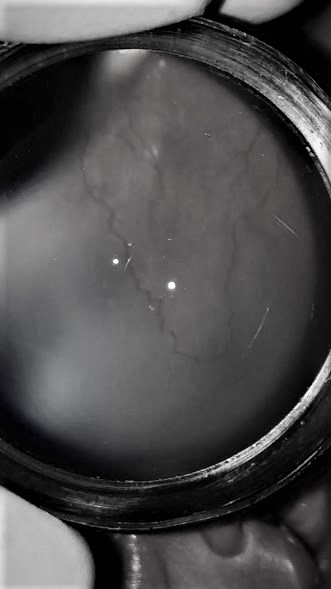

ANTIVEGF_13